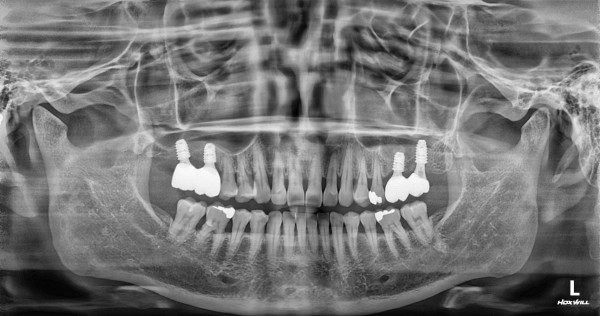

임플란트 센터 | 여) 48세